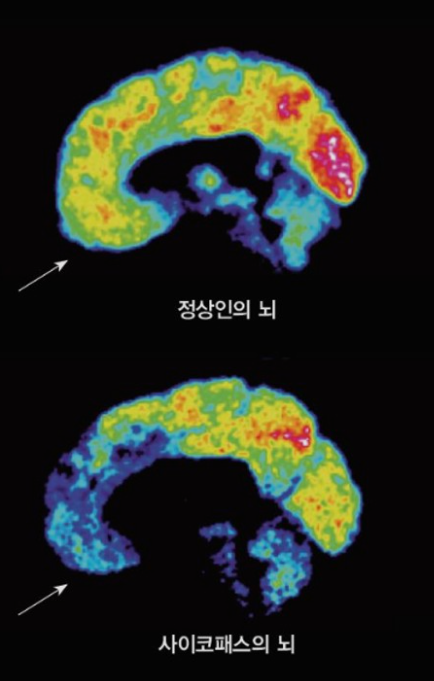

사이코패스 성향을 가진 범죄자들은 자신이 어떤 행동을 할 때, 그 행동을 하면 처벌을 받는지 안 받는지를 제대로 판단하지 못하는 것으로 나타났습니다. 세일라 호지스 몬트리온 대학 의대 교수팀은 사이코범죄자들의 재범률이 높은 이유를 맑히기 위해 사이코패스 범죄자들의 뇌를 자기 공명 영상 장치로 촬영하여 강력 범죄자, 사이코패스 범죄자, 일반일을 대상으로 각각 검사를 진행했습니다. 사이코패스 범죄자들은 사회적인 감정을 처리하는데 관여하고 있는 전문 측 전두피질과 측두극 부위가 수축돼 있는 것을 발견하였습니다. 연구팀은 사이코패스 범죄자들의 이 부분이 문제가 생기면서, 처벌을 통해 학습하지 못하는 것이라고 설명했습니다.